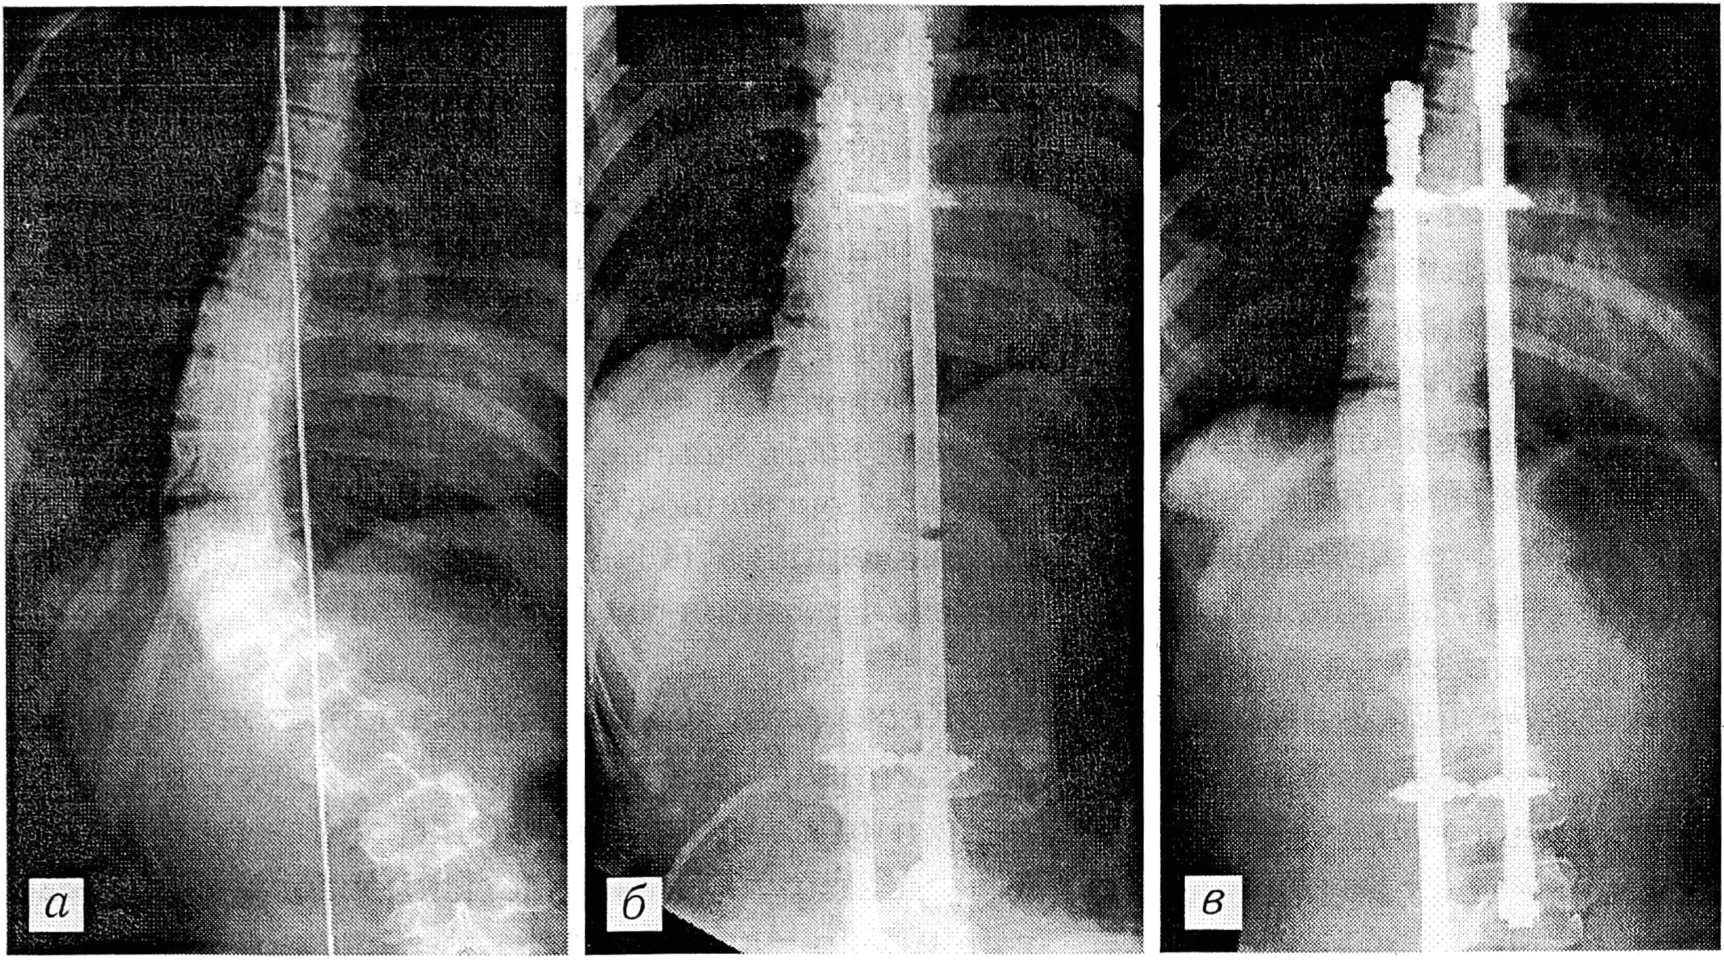

Клинический пример. Больная О.,14 лет, вторичные половые признаки выражены достаточно, месячные регулярные, тест Риссера 4. Диагноз: правосторонний грудопоясничный диспластический сколиоз II степени, тип 4 по King. До операции величина основного искривления 58°, патологическая ротация 35°, декомпенсация туловища 40 мм вправо (рис. 2, а). Произведена операция: коррекция искривления позвоночника рамочной конструкцией, задний спондилодез аутотрансплантатами по Геле- Уитмену. После операции величина основного искривления 20°, патологическая ротация 25°, декомпенсации туловища нет (рис. 2, б). Через 1 год после операции величина основного искривления 26°, патологическая ротация 26°, декомпенсации туловища нет (рис. 2, в). Операционная коррекция основного искривления 38° (65,5%), патологической ротации 10° (27%), декомпенсации туловища 40 мм (100%). Потеря операционной коррекции основного искривления 6° (15,7%), патологической ротации 1° (3,4%), декомпенсации туловища 0.

Рис. 2. Рентгенограммы больной О. до операции (а), непосредственно после операции (б) и спустя 1 год после операции (в).